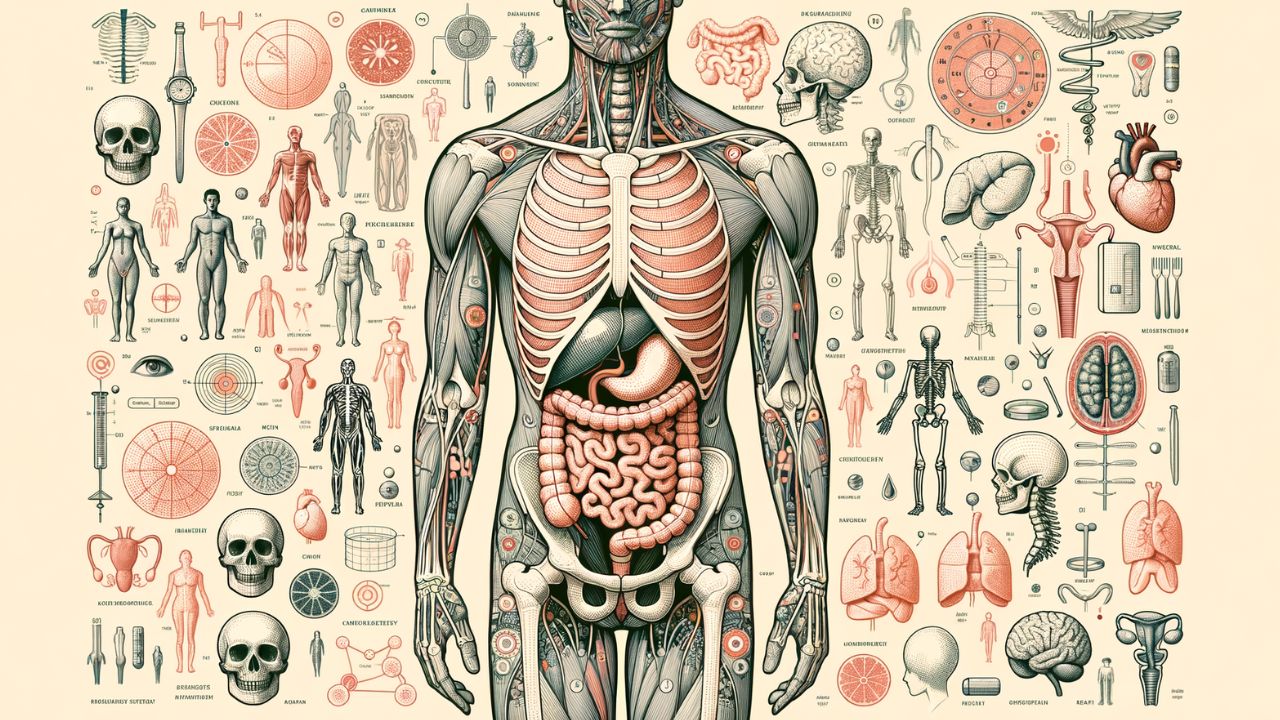

Ako dobre poznáte ľudské telo? Otestujte sa v dnešnom kvíze!

Tento kvíz je zameraný na ľudské telo a jeho fascinujúce zložky. V desiatich otázkach preveríme vaše znalosti o anatómii, fyziológii a funkciách jednotlivých orgánov a systémov. Zistite, ako dobre poznáte ľudské telo – od kostí až po činnosť jednotlivých orgánov. Tento kvíz je ideálny pre každého, kto sa zaujíma o biológiu, medicínu alebo jednoducho chce vedieť viac o tom, ako funguje jeho vlastné telo.